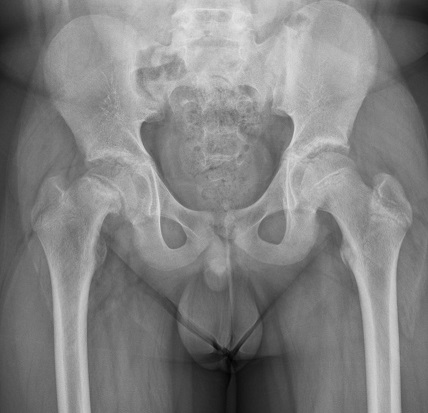

【112-2 醫學(四) 第74題】某病人常抱怨右側髖關節疼痛且走路一拐一拐的。門診的X光片影像如圖所示,下列敘述何者錯誤?

詳解

破題關鍵

這張X光片顯示右側股骨頭(femoral head)扁平、硬化且形狀不規則,這是典型的股骨頭缺血性壞死(Legg-Calvé-Perthes disease, LCPD)的表現。題目要求找出關於此疾病的「錯誤」敘述。

選項拆解